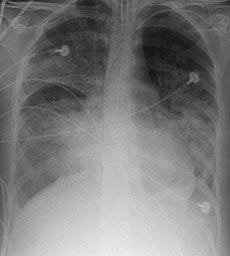

(image: Wikipedia)

An expert panel announced a new definition and severity classfication system for acute respiratory distress syndrome (ARDS) that aims to simplify the diagnosis and better prognosticate outcomes from the life-threatening pulmonary illness.

Bilateral opacities consistent with pulmonary edema must be present but may be detected on CT or chest X-ray.

The new Berlin definition for ARDS categorizes it as being mild, moderate, or severe: ARDS Severity PaO2/FiO2* Mortality** Mild 200 - 300 27% Moderate 100 - 200 32% Severe < 100 45% *on PEEP 5+; **observed in cohort There is no change in the underlying conceptual understanding of ARDS as an "acute diffuse, inflammatory lung injury, leading to increased pulmonary vascular permeability, increased lung weight, and loss of aerated lung tissue...[with] hypoxemia and bilateral radiographic opacities, associated with increased venous admixture, increased physiological dead space, and decreased lung compliance."